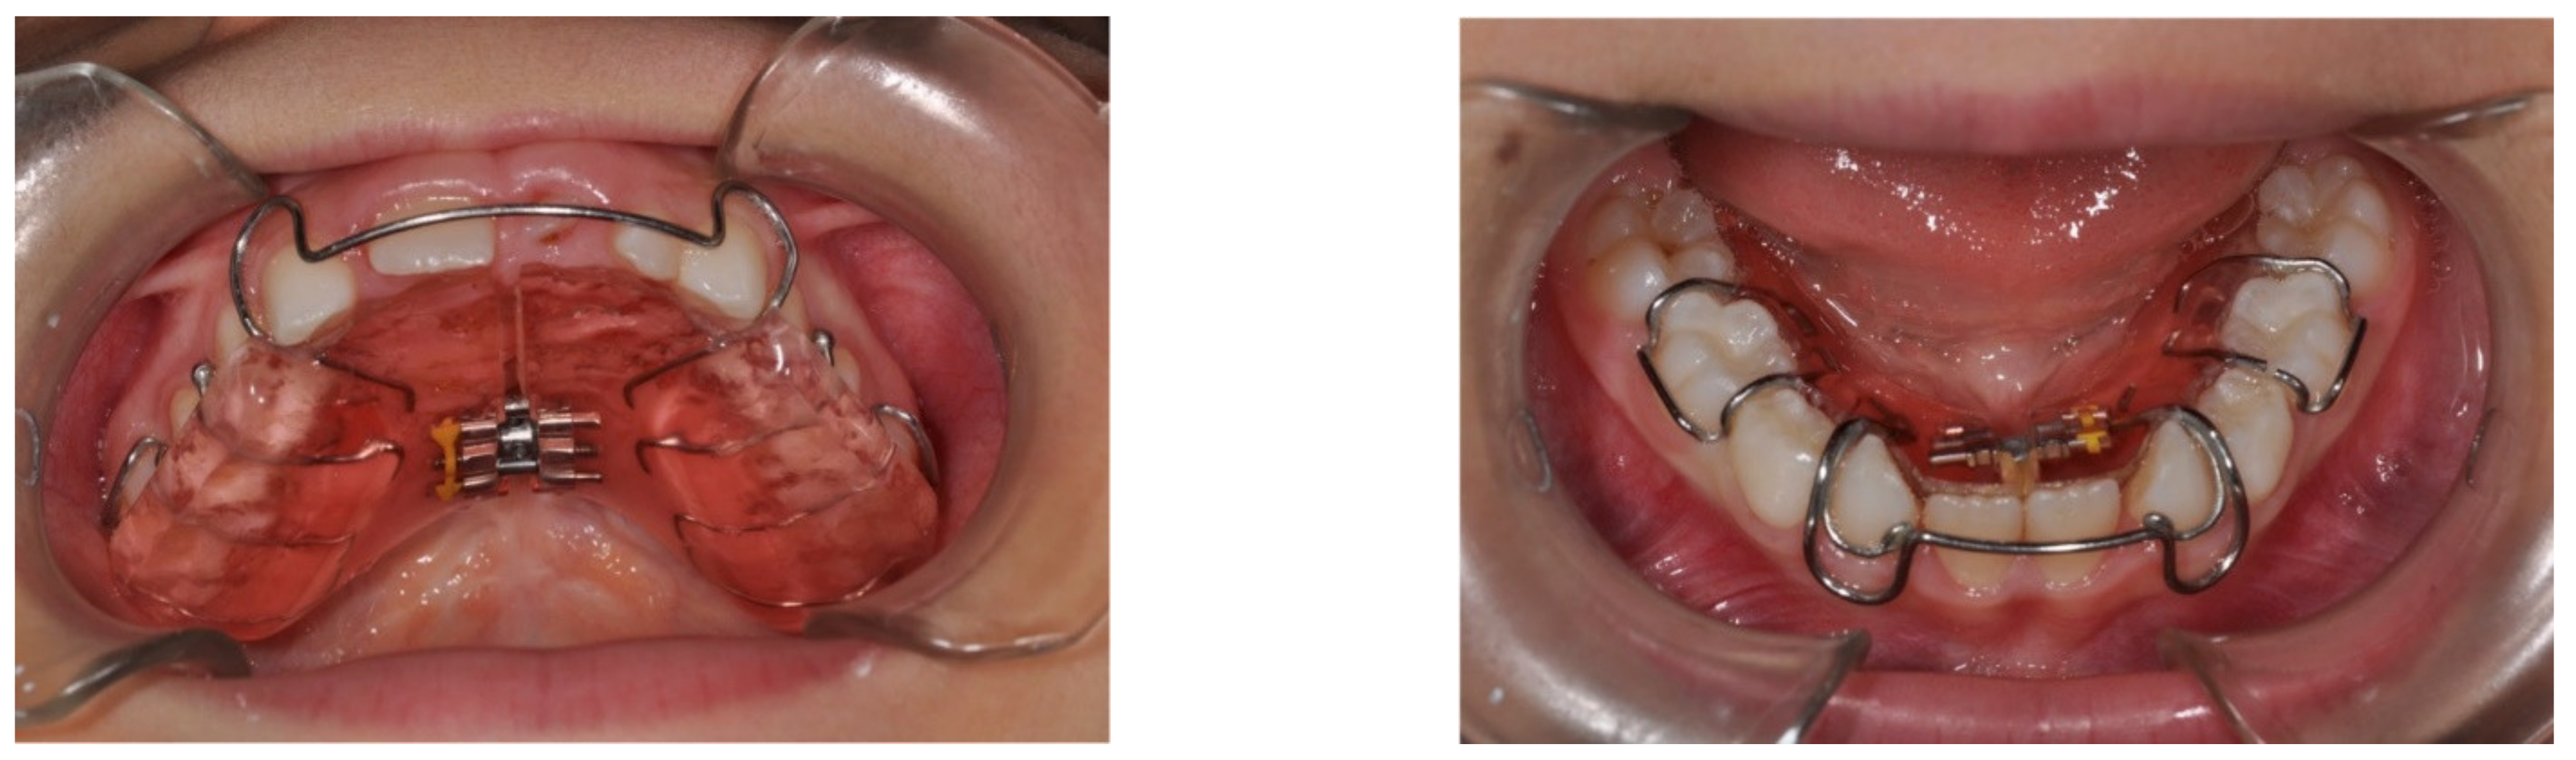

Proper prevention in the clinical management of hypodontia must therefore consider the evaluation of the growth control of the dentoalveolar arches, which will therefore require the use of removable orthodontic plates equipped with auxiliary elements such as sagittal and transverse screws for growth control (Figure 2).

Figure 2. Examples of orthodontic plates with transversal screw.